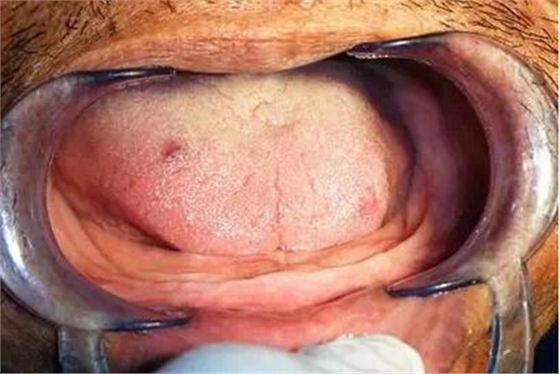

一、首先認(rèn)真檢查患者的口腔情況,觀察患者牙槽嵴的高度;覆蓋黏膜的情況;頰側(cè)黏膜反折處以及舌側(cè)口底的可利用范圍;舌體是否代償性增大;是否有舌后縮等情況;是否有口干、唾液分泌減少等癥狀。

這是我修復(fù)的一例牙槽嵴低平患者,采用的是滬鴿公司出品的無(wú)尖牙。

患者戴入后的穩(wěn)定性很好。

但患者總感到義齒咀嚼效率不高,吃飯時(shí)下頜黏膜常常疼痛。讓患者復(fù)診,患者說(shuō)她戴了幾十年的假牙,這點(diǎn)事情自己就搞定了,用刀子修改后就不再?gòu)?fù)診了。(不建議患者自己修改處理。)

同患者的家屬進(jìn)行了回訪,感到患者在使用中還是不太滿(mǎn)意。